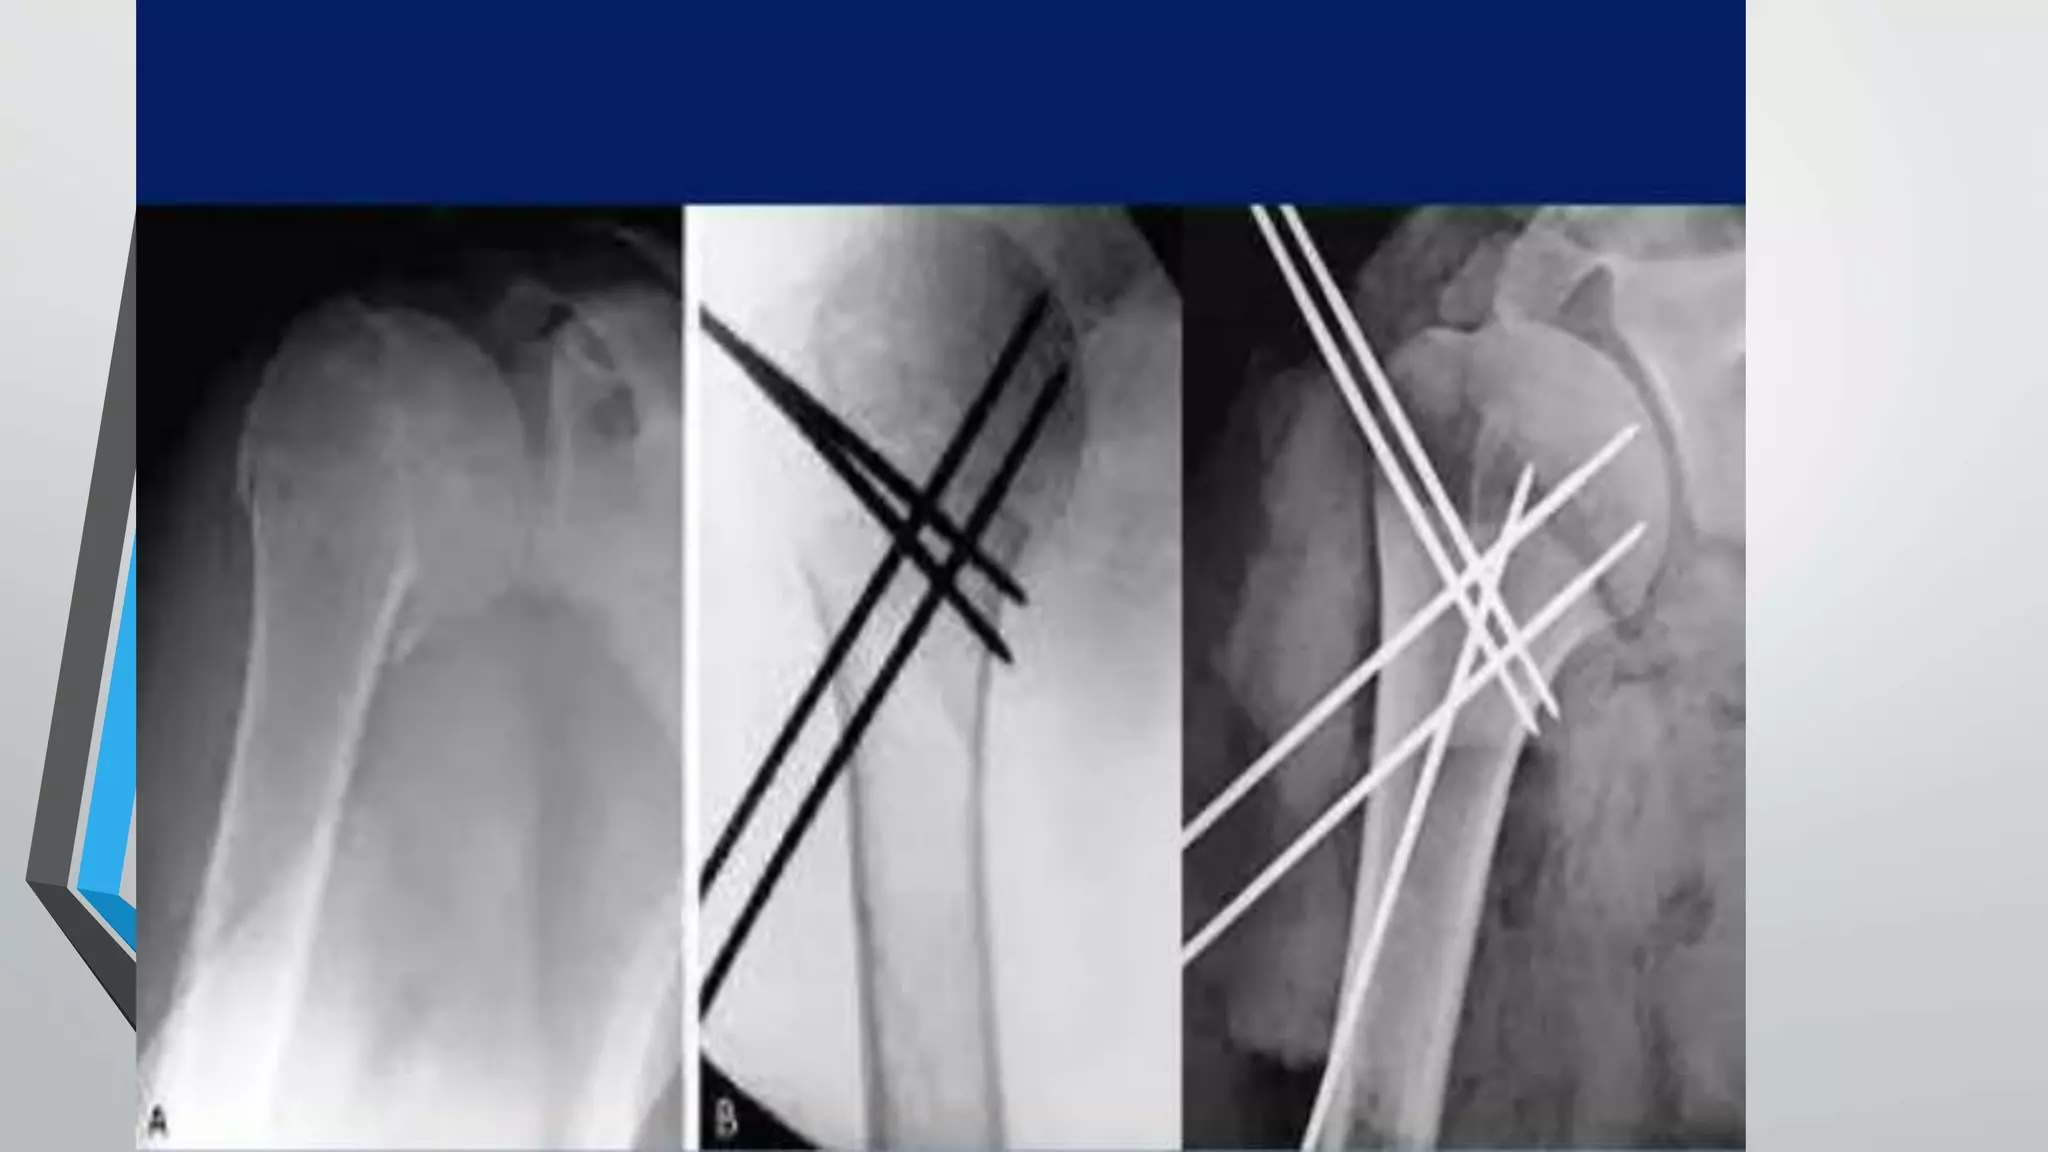

• For percutaneousK wiring CR by manual traction and mobilisation of the arm, then confirmed the reduction using an image intensifier. • An assistant maintained the reduction,and percutaneous pinning was performed. Three to five 2 –2.5 - mm K - wires were used for fracture fixation, depending on the stability. The K-wires were left protruding from the skin.

• To avoidinjury to axillary nerve ,lateral pins should enter the humeral cortex at a point at least twice the distance from the upper aspect of the head to the inferior head margin with a wire angulated 45degree to the cortical surface • The end point for the greater tuberosity pin should be >2cm from the inferior most margin of the humeral head